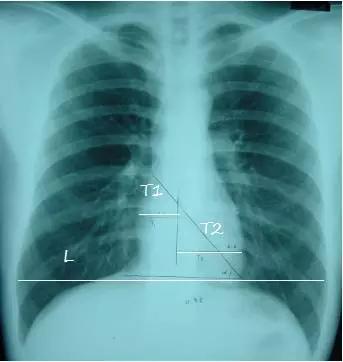

T1:心脏最右缘至前正中线距离

T2:心脏最左缘至前正中线距离

L :通过膈肌顶部至两侧胸廓内沿并平行于膈肌的线

心胸比 = (T1+T2) / L

- 正常<= 0.50

- 轻度增大 0.51-0.55

- 中度增大 0.56-0.60

- 重度增大 >= 0.60